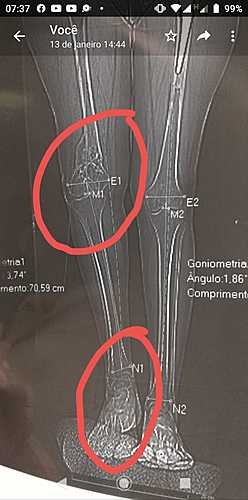

⚠️É necessário uma cirurgia do joelho esquerdo, devido o acidente, e uma cirurgia com alguns erros, seu joelho ficou de lado, e o osso colou assim, com isso ela perdeu toda sua articulação, e o líquido que lubrifica durante os movimentos, e virtude disso  o contato é osso com osso,  gerando  muita dor, e também mais desgastes ósseo. Fig 1.

A cirurgia será realizada em Maringá PR, devido a sua complexidade, e por Rondônia não ter bancos de ossos. O que tudo indica é que por esse osso  está fino a prótese não suportaria, tendo a necessidade de enxerto ósseo .

😱A Tida também teve fratura de bacia, e fêmur,  ela hoje tem uma diferença de 3cm  de uma perna para outra. Fig 2